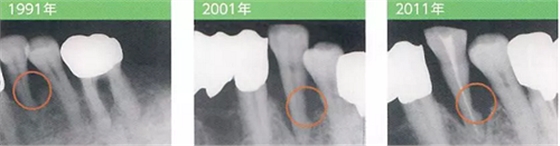

病例3 雖然只進(jìn)行了一次SRP,但預(yù)后發(fā)生了巨大改變

1991年

左下4有較深的牙周袋和BoP,因此用手動(dòng)刮治器進(jìn)行了徹底的SRP。SRP后患者數(shù)次來(lái)復(fù)診,每次都反應(yīng)有牙齒過(guò)敏,最后就不來(lái)醫(yī)院了。

2001年

SRP后10年,由于劇烈的疼痛前來(lái)就診希望進(jìn)行拔髓。雖然只進(jìn)行了一次SRP,但是左下4的牙根遠(yuǎn)中面出現(xiàn)了明顯的缺損。

2011年

在感染控制的前提下,10年間持續(xù)進(jìn)行了牙菌斑去除,沒(méi)有再發(fā)現(xiàn)BoP。牙周袋也閉鎖了。但是遠(yuǎn)中面硬組織的缺損仍然發(fā)展顯著。